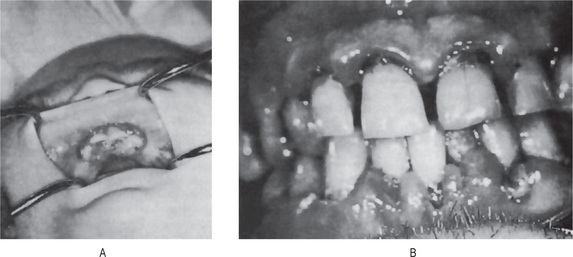

The oral effects of vitamin C deficiency in humans occur chiefly in the gingival and periodontal tissues. The interdental and marginal gingiva is bright red with a swollen, smooth, shiny surface. In fully developed scurvy the gingiva becomes boggy, ulcerates and bleeds. The color changes to a violaceous red. In infants the enlarged tissue may cover the clinical crowns of the teeth (Fig. 15-12). In almost all cases of acute or chronic scurvy the gingival ulcers show the typical organisms, and the patients have the typical foul breath of persons with fusospirochetal stomatitis. In the severe chronic cases of scurvy, hemorrhages into and swelling of the periodontal membranes occur, followed by loss of bone and loosening of the teeth, which eventually exfoliate.

Figure 15-12 Vitamin C deficiency or scurvy in an infant (A) and an adult (B). A, Courtesy of Dr EV Zegarelli; B, Courtesy of Dr ER Costich.